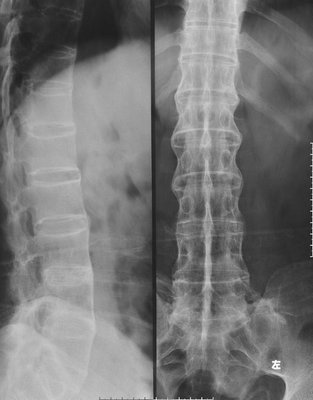

(图:X线片显示陈女士相邻椎体连接成竹节样)

检查结果:CT检查结果:骶髂关节炎出现明显的软骨下骨质侵蚀、破坏,增生硬化,关节边缘呈毛刷状、锯齿状,关节间隙明显异常,韧带关节骨质破坏;脊柱X线检查结果:椎间盘间隙钙化、骨化、相邻的椎体连接成竹节样;辅助检查:轻度贫血。